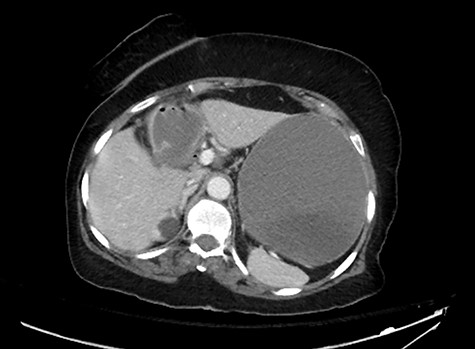

The extracted stone from the small bowel. Note that it was extracted as one piece.

The patient was taken to the operating room (OR) for diagnostic laparoscopy that revealed small bowel obstruction with a transition zone at the mid-ileum. An enterotomy proximal to the obstruction point was made and the stone was removed. The stone was round in shape, not faceted (Fig. 3). The rest of the bowel was examined from the Ligament of Treitz to the ileocecal valve with no other stones identified. No attempt was made to explore the right upper quadrant as there was no plan to take down the fistula during this surgery.